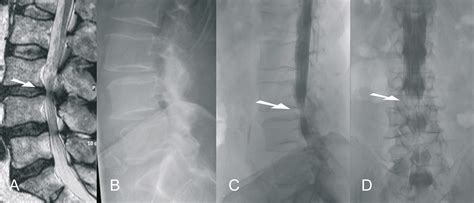

Ligamentum flavum buckling is a result of a weakened ligamentum flavum, or the ligaments in your vertebrae that allow for bending over and snapping back up. La ligamenta flava (singular, ligamentum flavum , latín para ligamento amarillo ) son una serie de ligamentos que conectan las partes ventrales de las. The key molecules and mechanisms responsible for hlf remain unclear. A layer of tissue that protects the spinal cord. This hypertrophy (thickening) occurs because of excess mechanical stress coming on ligament. Related online courses on physioplus. Any of a series of ligaments of yellow elastic tissue connecting the laminae of adjacent vertebrae from the axis to the sacrum. Function of ligamentum flavum function. Looking to download safe free latest software now. A ligament (= strong fibre) that helps connect the bones that make up the spine 2. Ligamentum flavum is an elastic ligament. Ligament that runs in between the laminae of two adjacent vertebrae. Hypertrophy of the ligamentum flavum (hlf) is one of the common causes of lumbar spinal stenosis (lss).